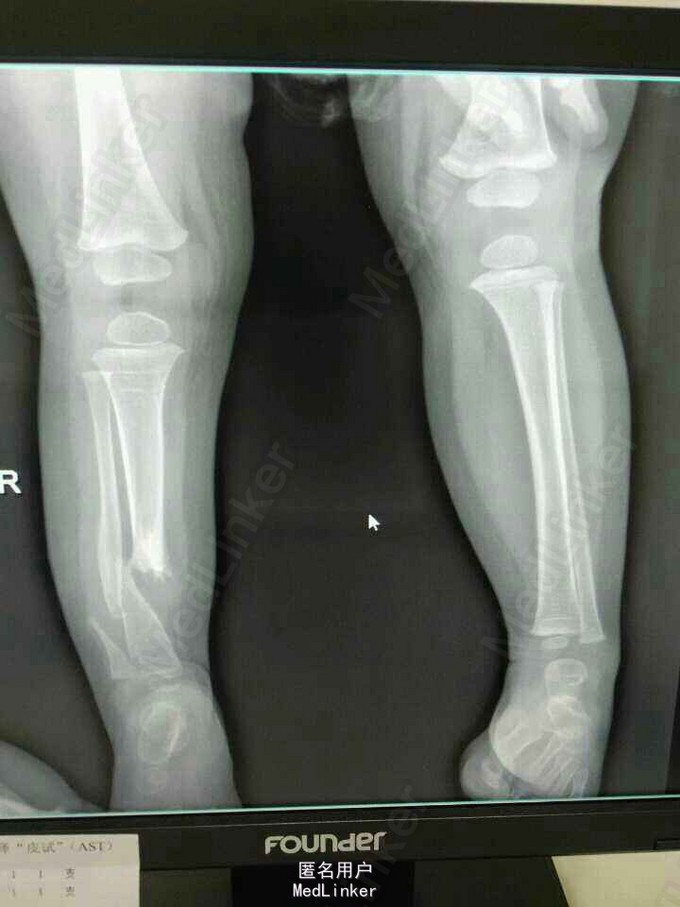

患女1岁8个月,患者母亲诉小孩出生时右小腿畸形,1岁时学走路跌倒后哭闹数天,小腿肿胀去医院检查示右胫腓骨折,稍做固定,1岁3个月时复查骨折未愈合,考虑先天性胫骨假关节,行手术治疗,现术后5个月复查未愈。目前小儿不能行走。

右下肢短缩约2cm,右小腿畸形,肌力检查不配合,

神经纤维瘤病,先天性胫骨假关节。该患者经过讨论及与家属多次沟通愈后情况,行病灶切除,取母体骨移植,AO锁定钢板内固定,暂时管型石膏外固定,并订制支具